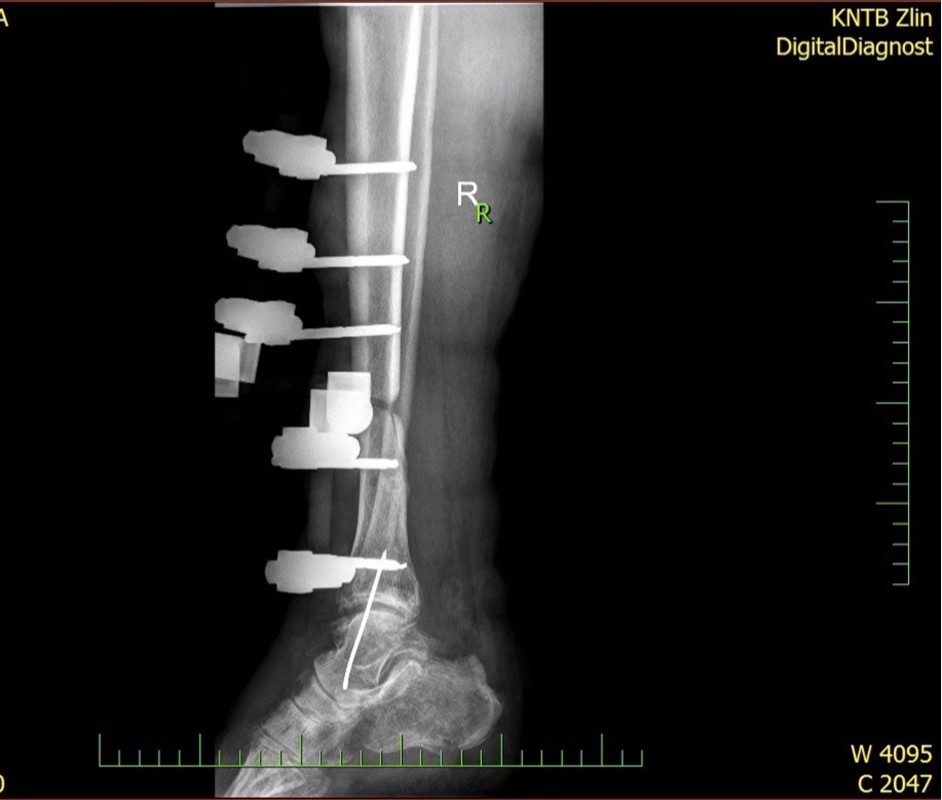

Figure 33. X-ray documentation of the whole treatment of tibia fracture. External fixation was used throughout the treatment until bone was healed. From 9.October 2015 to 2.February 2017